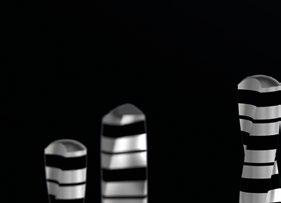

El propósito de este artículo es mostrar cómo el empleo de implantes de cuello convergente nos permite ser predecibles y simplificar casos complejos de manera inmediata en una sola cirugía gracias al diámetro estrecho de su cuello que aporta más espacio a los tejidos que van a ser regenerados y la versatilidad de poder realizar prótesis atornillada vertical con libertad de plataforma restauradora sobre la hipérbole. Asimismo, su cuello intramucoso mejora la estabilidad crestal gracias a los más de 2 mm de superficie UTM donde se estabiliza el tejido conectivo supracrestal generando estabilidad periimplantaria. Finalmente, los t-bases sin línea de terminación aportan libertad y sencillez al técnico de laboratorio para construir resturaciones estéticas no sujetas a plataformas restauradoras preestablecidas en altura y diámetro y a un nivel biológico de bajo riesgo.

La implantología en el sector anterior asociada a áreas de déficit óseo suponen un escenario clínico complejo no sólo para el cirujano, que en la mayoría de las ocasiones necesita varias intervenciones quirúrgicas para la recuperación de volúmenes óseos y manejo de tejidos blandos sino también para el prostodoncista donde la exigencia estética es alta y el control de la estabilidad biológica en áreas regeneradas supone un reto para la salud periimplantaria a largo plazo. El propósito de este artículo es mostrar cómo el empleo de implantes de cuello convergente nos permite ser predecibles y simplificar casos complejos de manera inmediata en una sola cirugía gracias al diámetro estrecho de su cuello que aporta más espacio a los tejidos que van a ser regenerados y la versatilidad de poder realizar prótesis atornillada vertical con libertad de plataforma restauradora sobre la hi-

pérbole. Asimismo, su cuello intramucoso mejora la estabilidad crestal gracias a los más de 2 mm de superficie UTM donde se estabiliza el tejido conectivo supracrestal generando estabilidad periimplantaria. Finalmente, los t-bases sin línea de terminación aportan libertad y sencillez al técnico de laboratorio para construir resturaciones estéticas no sujetas a plataformas restauradoras preestablecidas en altura y diámetro y a un nivel biológico de bajo riesgo.

Apical a esta plataforma queda un cuello tratado específicamente (UTM) para su convivencia con el conectivo supracrestal mejorando la estabilidad de dichas futuras fibras gracias a la convergencia a coronal de los 3 mm de cuello y que en los primeros estadios de cicatrización aportan espacio para el biomarterial y el injerto de tejido conectivo sin que existan presiones nocivas (Figuras 6 y 7).

Este cuello convergente hará las veces de pilar intermedio colocado en protocolo de one abutment one time y con la mejor conexión que se puede emplear a ese nivel de profundidad que es la que no existe ya que se trata de un implante intramucoso de una sola pieza, esto genera una gran estabilidad biomecánica y nula filtración bacteriana (Figura 8).